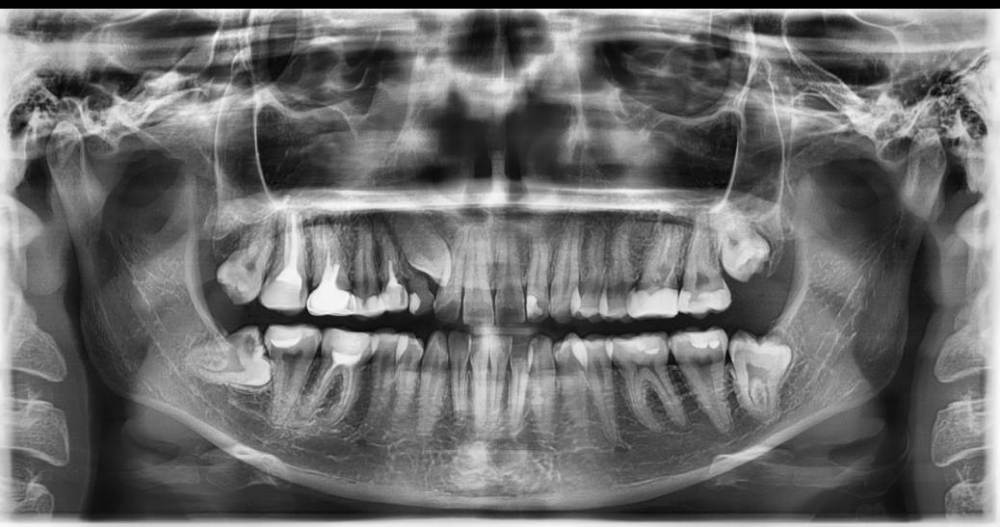

Bobik007 Опубликовано 2 мая, 2021 Поделиться Опубликовано 2 мая, 2021 Всем привет. В челюсти проживает ретинированный клык, а на его законном месте все еще молочный. Была у ортодонта, но врач сказала, что есть вероятность того, что клык не пойдет (возраст - 26 лет). Вот теперь не знаю, есть ли смысл вообще в это дело ввязываться. Как считаете? Ссылка на комментарий

АнтонТЛТ Опубликовано 2 мая, 2021 Поделиться Опубликовано 2 мая, 2021 Возраст не особо важен, более важна форма корня клыка. Если корень загнутый, то скорее всего нормально не получится вытянуть. Ссылка на комментарий

Bobik007 Опубликовано 2 мая, 2021 Автор Поделиться Опубликовано 2 мая, 2021 Спасибо за информацию, насчет корня пока не знаю. Основное ее переживание в том, что он слишком присоседился к двойке Ссылка на комментарий

АнтонТЛТ Опубликовано 2 мая, 2021 Поделиться Опубликовано 2 мая, 2021 Компьютерную томограмму нужно сделать Ссылка на комментарий